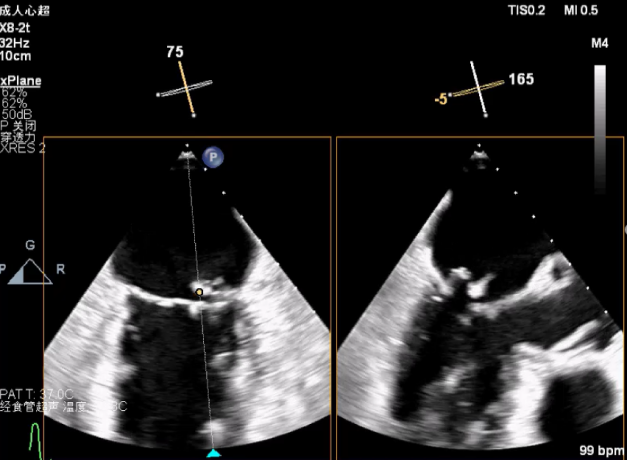

2D视图下进第二个夹子

将第二个夹子置于第一个夹子外侧并调整Orientation

成功抓捕外侧残余脱垂区域瓣叶

第二个夹子外侧残余小束分流,宽3.7mm

3D视图两个夹子近似并排排列,第二个夹子外侧小残余脱垂,瓣叶裂孔已不明显